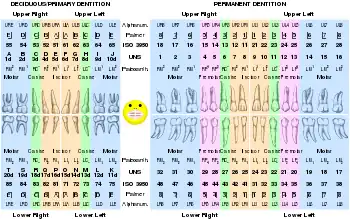

Numbering systems

There are several different dental notation systems for associating information to a specific tooth. The three most commons systems are the FDI World Dental Federation notation, Universal numbering system (dental), and Palmer notation method. The FDI system is used worldwide, and the universal is used widely in the United States.

Although the Palmer notation was supposedly superseded by the FDI World Dental Federation notation, it overwhelmingly continues to be the preferred method used by dental students and practitioners in the United Kingdom.[6] It was originally termed the "Zsigmondy system" after the Austrian dentist Adolf Zsigmondy who developed the idea in 1861, using a Zsigmondy cross to record quadrants of tooth positions.[7] The Palmer notation consists of a symbol (┘└ ┐┌) designating in which quadrant the tooth is found (from the dentist's perspective) and a number indicating the position from the midline. Permanent teeth are numbered 1 to 8, and primary teeth are indicated by a letter A to E.

The universal numbering system uses a unique letter or number for each tooth. The uppercase letters A through T are used for primary teeth and the numbers 1 - 32 are used for permanent teeth. The tooth designated "1" is the right maxillary third molar and the count continues along the upper teeth to the left side. Then the count begins at the left mandibular third molar, designated number 17, and continues along the bottom teeth to the right side.

The FDI system uses a two-digit numbering system in which the first number represents a tooth's quadrant and the second number represents the number of the tooth from the midline of the face. For permanent teeth, the upper right teeth begin with the number, "1". The upper left teeth begin with the number, "2". The lower left teeth begin with the number, "3". The lower right teeth begin with the number, "4". For primary teeth, the sequence of numbers goes 5, 6, 7, and 8 for the teeth in the upper right, upper left, lower left, and lower right respectively.

As a result, any given tooth has three different ways to identify it, depending on which notation system is used. The permanent right maxillary central incisor is identified by the number "8" in the universal system. In the FDI system, the same tooth is identified by the number "11". The palmer system uses the number and symbol, 1┘, to identify the tooth. Further confusion may result if a number is given on a tooth without assuming (or specifying) a common notation method. Since the number, "12", may signify the permanent left maxillary first premolar in the universal system or the permanent right maxillary lateral incisor in the FDI system, the notation being used must be clear to prevent confusion.

In 1891 Victor Haderup devised a variant of eight tooth quadrant system in which plus (+) and minus (-) were used to differentiate between upper and lower quadrants, and between right and left quadrants (e.g., +1 = upper right central incisor; 1- = lower left central incisor). Primary teeth were numbered as upper right (05+ to 01+), lower left (-01 to -05). This system is still used in Denmark.[8]